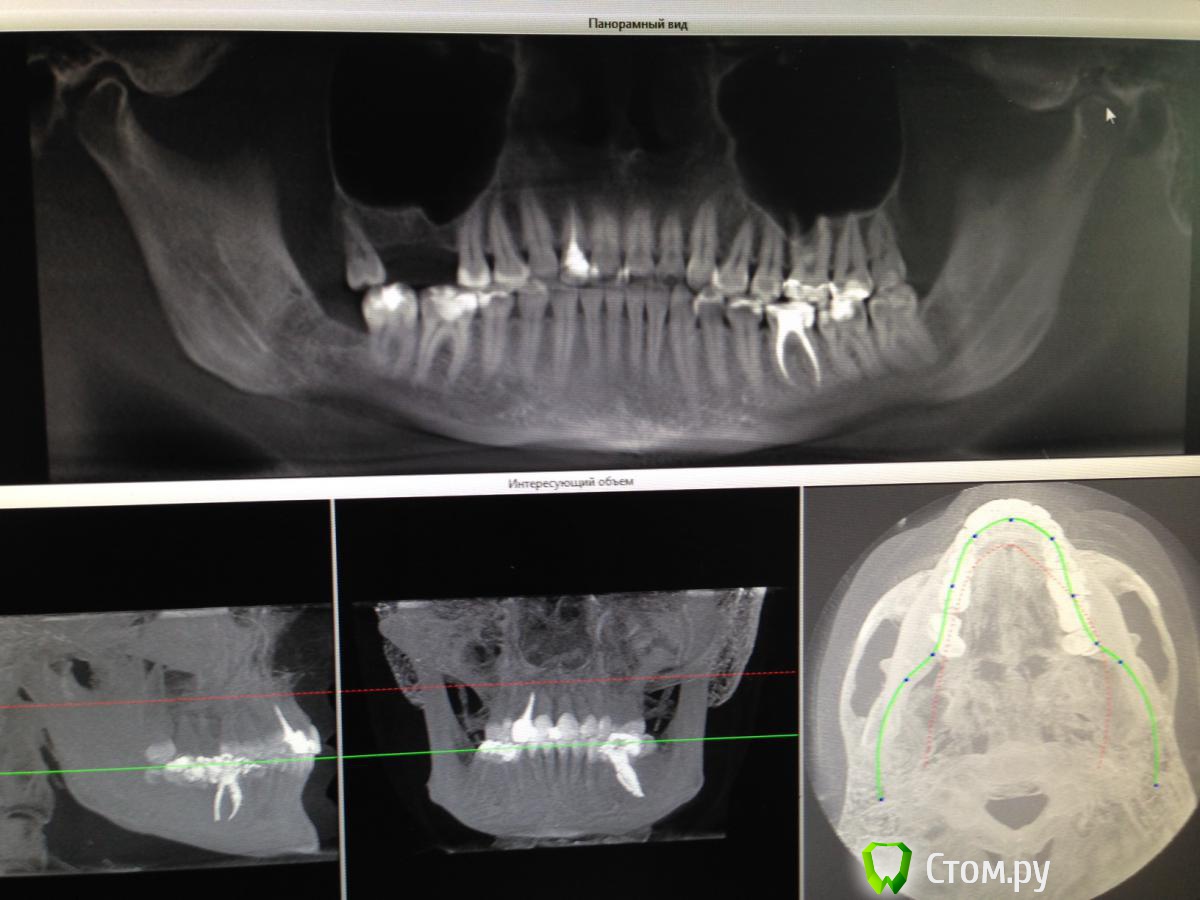

Майло Опубликовано 17 февраля, 2014 Автор Поделиться Опубликовано 17 февраля, 2014 (изменено) Попыталась загрузить снимок кт который был сделан до операции и еще один на всякий случай отснятый на телефон. Изменено 17 февраля, 2014 пользователем Майло Ссылка на комментарий

Майло Опубликовано 18 марта, 2014 Автор Поделиться Опубликовано 18 марта, 2014 (изменено) Здравствуйте, наконец сделала кт. Сегодня появилась небольшая боль над правой бровью (после лазера прошла, к вечеру появилась опять). Насморк и заложенность присутствуют. Еще сегодня опять поговорила со своим хирургом имплантологом. По симптомам сказал, что похоже присоединилась какая-то лор болячка и наверное надо сходить к лору. По кт сказал, что все нормально. Немного сужена пазуха справа, но учитывая, что я аллергичная, это нормально. Про капли типа Полидекса, сказал спросить у лора. Завтра я делаю последний лазер, по прежнему промываю нос Отривином Бэби (мне так удобней), пью кларитин, "выбиваю" нос по необходимости, но стараюсь пореже (2-3 раза в день). Еще он отдал кт через 2 недели после имплантации, на всякий случай прикреплю и этот снимок. Самый первый снимок кт был сделан через 2 недели после имплантации. Второй и третий сегодня. Подскажите, я так понимаю данное кт не показывает есть ли у меня гайморит? (к лору смогла записаться аж на 26-е) И все равно хотелось бы узнать ваше мнение по поводу состояния имплантов, есть ли там воспаление или "нагноение"? Изменено 18 марта, 2014 пользователем Майло Ссылка на комментарий

Майло Опубликовано 18 марта, 2014 Автор Поделиться Опубликовано 18 марта, 2014 (изменено) Решила еще добавить пару кадров своих пазух, вначале показалось что справа что-то есть (рис1), потом поняла это костный материал и импланты (рис2). Надеюсь так должно быть. И еще вопрос, может и "тупой", такое яркое свечение имплантов, особенно заметно на фото в профиль, это нормально? Изменено 18 марта, 2014 пользователем Майло Ссылка на комментарий